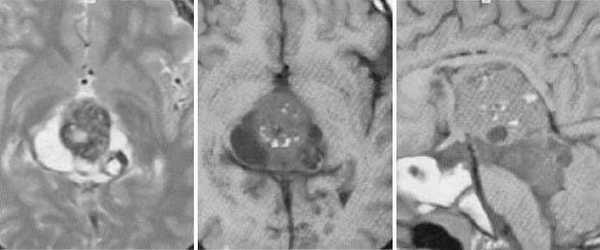

Пинеобластома. В режиме Т2 и Т1 выявляется опухоль задних отделов III желудочка мозга с развитием окклюзионной гидроцефалии. В строме опухоли небольшой участок подострого кровоизлияния. После в/в контрастирования опухоль интенсивно и достаточно гомогенно накапливает контрастирующее вещество.

Герминома пинеальной области. На Т2 ВИ опухоль имеет слабо гиперинтенсивный сигнал по сравнению с тканью мозга, тогда как на Т1 опухоль практически изоинтенсивна с мозгом. Желудочковая система гидроцефально расширена. III желудочек деформирован. Четверохолмная пластинка оттеснена кзади.

Герминома пинеальной области. Опухоль имеет гетерогенное строение с множеством мелких и крупных кист. Вокруг опухоли определяется перифокальный отек.

Злокачественная смешанная герминативноклеточная опухоль. В боковых желудочках и пинеальной области определяются множественные опухолевые узлы с выраженным перитуморальным отеком. Внутрижелудочковые образования с признаками кровоизлияний. При в/в контрастировании определяется выраженное контрастирование узлов. Дополнительно визуализируется метастазирование по эпендиме боковых и IV желудочков мозга.